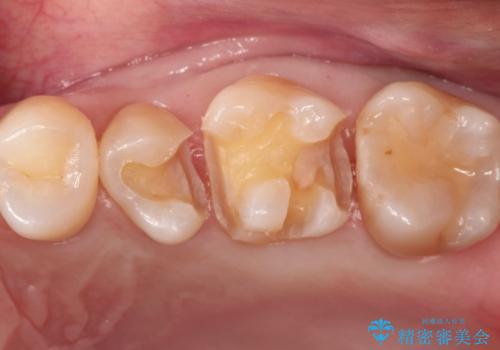

- 歯と歯の間で見つかりづらい虫歯でしたが、顕微鏡で確認し患者様に説明することで理解していただき、セラミックインレーにて修復治療を行いました。

以前にプラスチックの材料で修復した箇所が虫歯として見つかることはよくあります。

当院でのセラミックインレーは必ずラバーダム防湿を行なって装着しております。